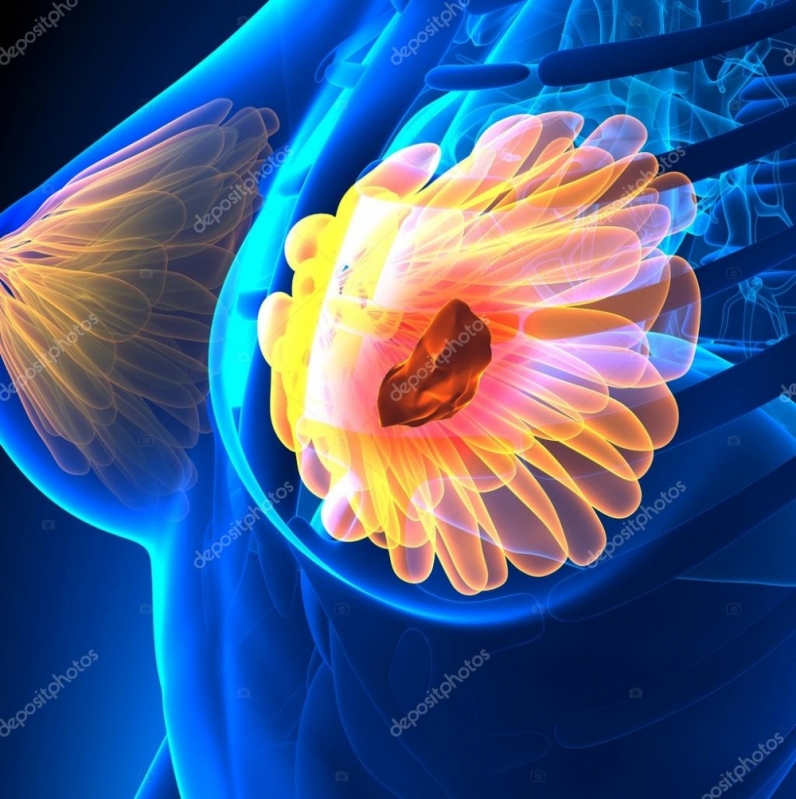

médico que trata mama perto Cidade Jardim oferece prevenção, diagnóstico, tratamento e reabilitação para pacientes com câncer de mama. Além disso, o autoexame não é suficiente para perceber o surgimento de doenças, por isso, o procedimento deve ser realizado por um profissional.